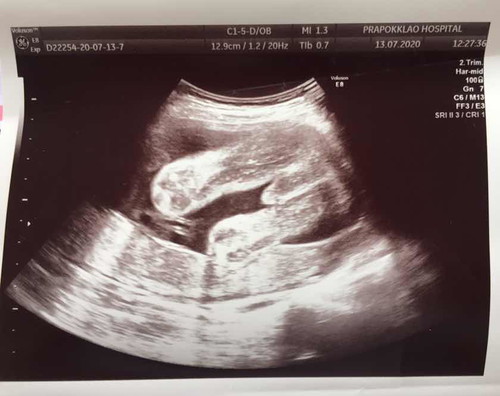

แบบนี้ ญ หรือ ช กันนร้า ? แม่ๆช่วยดูหน่อย !

คิดว่าผู้ชายนะค่ะ ของเราก้อเป็นเเบบนี้เเหละค่ะ

จอนี้ชัดจริง ชายแท้แน่นอน

บ้านนี้ผู้หญิงคะ

น่าจะผู้ชายนะคะ

ผู้ชายค่ะ